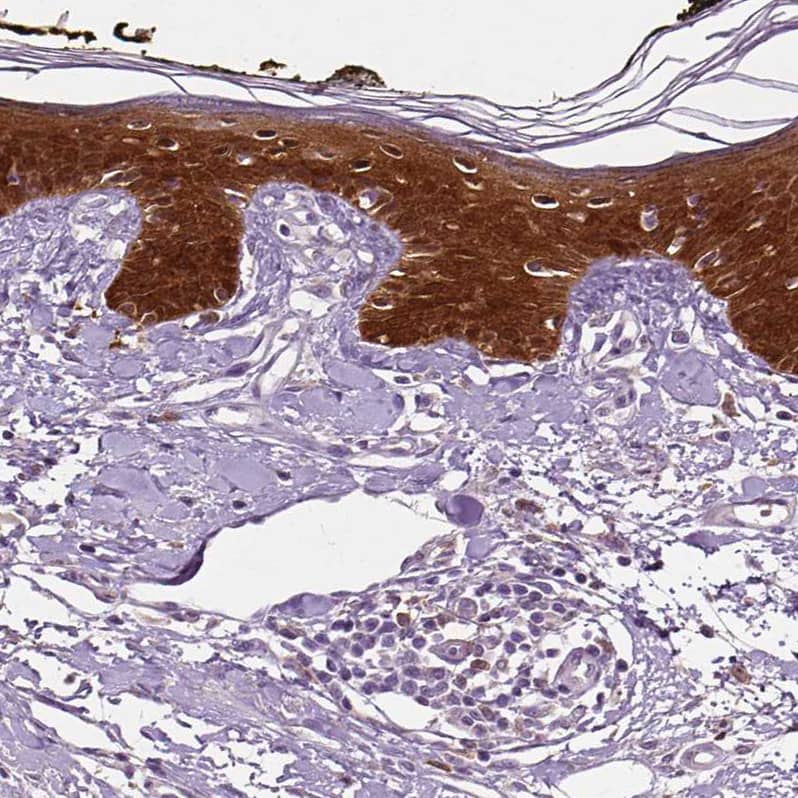

Staining of human skin shows strong cytoplasmic positivity in squamous epithelial cells.